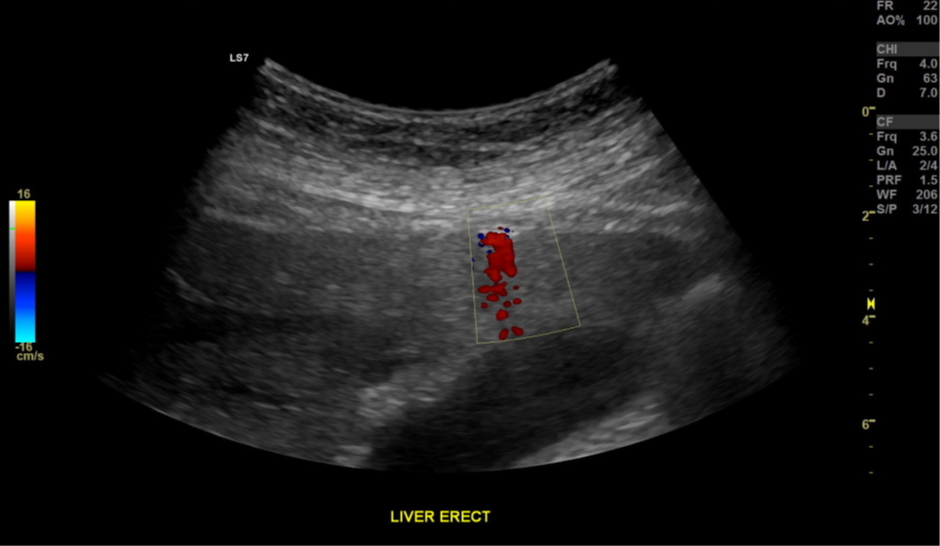

Figure 3. |

The presence and recognition of the twinkling artifact behind gas can increase diagnostic confidence.